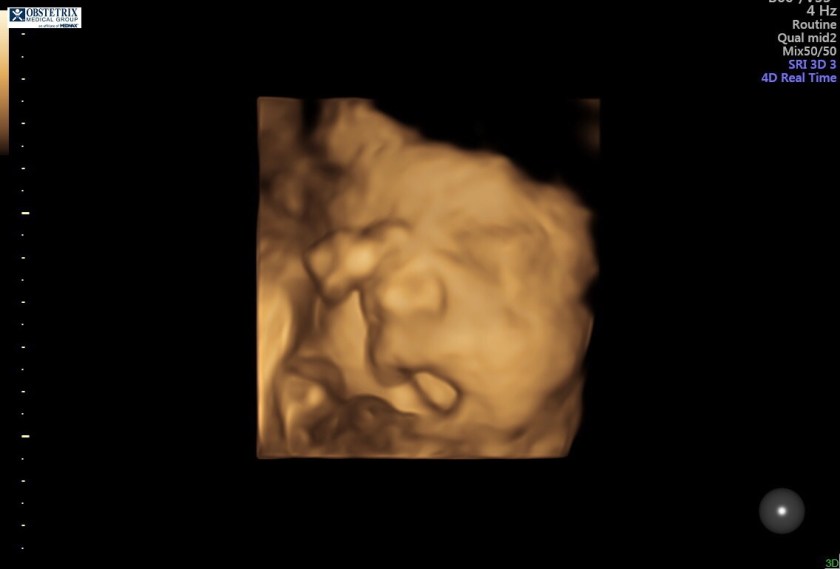

Itās been quite a while since I last posted on here, and our family has changed quite a bit! My daughter is now in Kindergarten, while my son⦠who I was pregnant with when I started this blog⦠goes to Kindergarten next year! Oh yeah, and we have another baby on the way! Due Spring of 2019.